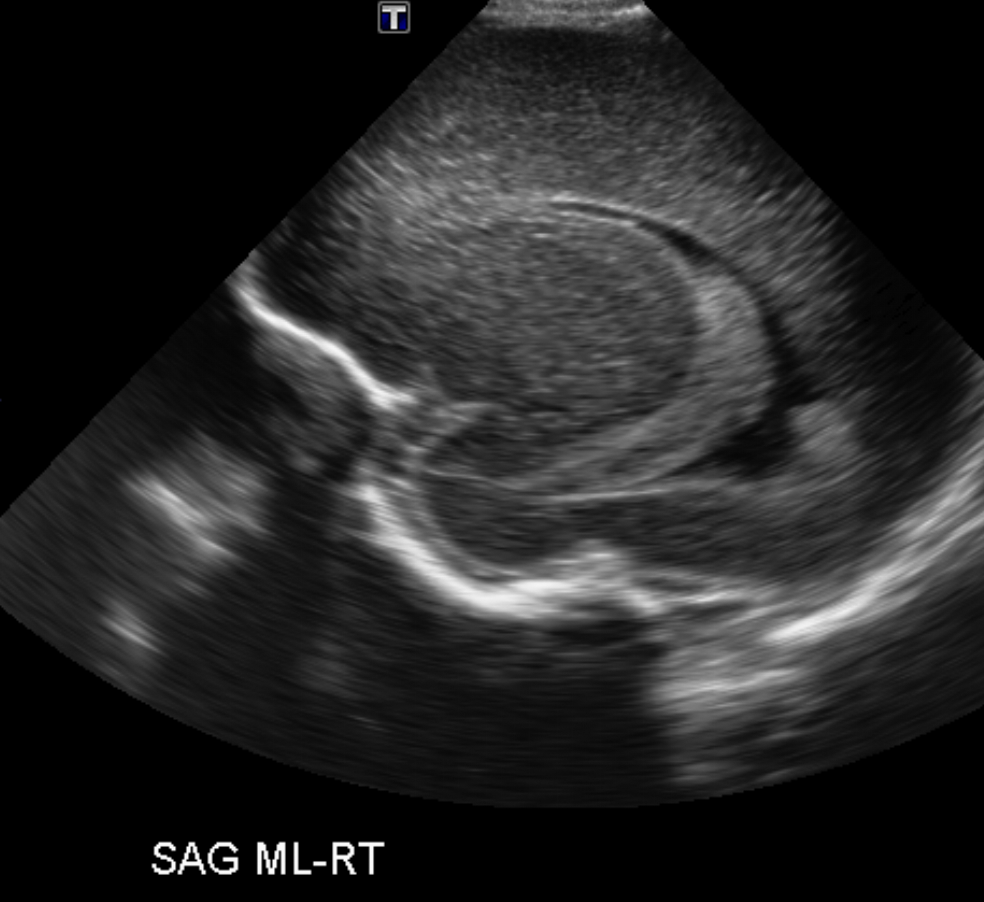

CSF spaces/ventricular system

There is a prominence of the extra axial fluid spaces. [Yes/No]

There are debris/septations in the extra axial fluid spaces. [Yes/No]

There are debris/septations in the ventricles. [Yes/No]

There is a subdural collection on the right/left side. [Yes/No]

There is prominence of the ventricular system. [Yes/No]

There is an asymmetry of the ventricular system. [Yes/No]

There is a cavum septum pellucidum. [Yes/No]

There is a midline shift towards right/left. [Yes/No]

The choroid plexus is bulky/lobulated. [Yes/No]

There is a choroid plexus cyst measuring… [Yes/No]

There are debris/clots in the occipital horn. [Yes/No]

There is a posterior fossa cyst measuring… [Yes/No]

The tentorium is elevated/depressed. [Yes/No]

The lateral ventricle/s are dilated. [Yes/No]

The third ventricle is dilated. [Yes/No]

The 4th ventricle is dilated. [Yes/No]

There are pseudo cysts. [Yes/No]